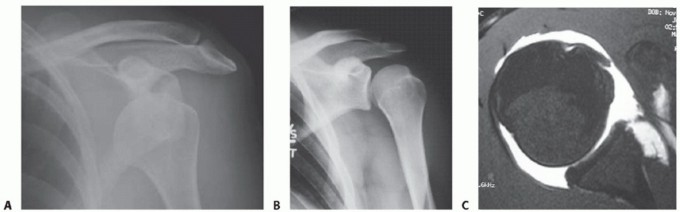

FIG 2 • A. The Bankart lesion: tear of the anterior inferior glenoid labrum. B. Axial view MRI scan showing the ALPSA. C,D. CT scan with axial view and reconstruction image, respectively, showing a large anterior inferior glenoid bony Bankart fracture.

The “essential anatomic defect,” or Bankart lesion, first described by British pathologist A. Blundell Bankart in 1923, describes an avulsion of the anterior labrum and anterior band of the IGHL from the anteroinferior glenoid, typically as a result of a traumatic anterior shoulder dislocation (FIG 2A).

The labrum may also be avulsed from the glenoid rim as part of a sleeve of tissue that includes glenoid

periosteum (anterior labral periosteal sleeve avulsion [ALPSA]) (FIG 2B).23 In these cases, the tissue displaces medially and may heal to the medial glenoid neck, with subsequent instability if left uncorrected.

Osseous fracture of the anterior inferior glenoid rim (“bony

Bankart” lesion) or more subtle attritional changes or glenoid wear may contribute to instability as well (FIG 2C).

In one study, three-dimensional (3-D) computed tomography (CT) identified bony changes in 90% of patients with recurrent anterior instability.27,33

Anterior or inferior bone loss of greater than 25%, resulting in a glenoid with an “inverted pear” appearance is associated with significantly increased risk of instability, often requiring reconstitution of the bony arc via either

primary repair or bony augmentation27 (FIG 2D*).

Radiographs include anteroposterior (AP), lateral, and axillary views (FIG 3A,B). The axillary view is particularly important for assessing anterior glenoid rim defects.

CT scan is not necessary in all cases but may be helpful in identifying patients with bony defects. Sagittal cuts and 3-D reconstructions are useful for quantifying the extent of glenoid bone loss (see FIG 2C,D).

Magnetic resonance imaging (MRI) scan is not necessary in all cases but can be useful in identifying labral lesions as well as concomitant rotator cuff tears (FIG 3C) or nondisplaced tuberosity fractures, which are more commonly seen in dislocations in patients older than 50 years of age.